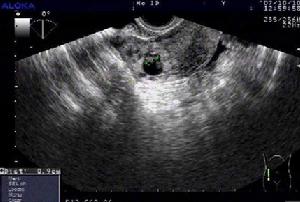

子宮輸卵管碘油造影。是診斷生殖器結核的較常用方法,一般於月經乾淨後3~7日內進行。可顯示如下特徵:①子宮腔呈不同程度的狹窄或畸形,邊緣呈鋸齒狀;②輸卵管管腔多處狹窄如串珠樣,或管腔細小而僵直;③在相當於盆腔輸卵管、卵巢、淋巴結的部位有鈣化灶;④若造影劑進入子宮一側或兩側靜脈叢,應考慮有子宮內膜結核的可能。雖然子宮輸卵管碘油造影對生殖器結核的診斷意義較大,但該操作有可能將輸卵管管腔中的乾酪樣物質或結核菌帶入腹腔,因此造影前後應使用抗結核藥物,結核活動期應避免該項檢查。超聲檢查 可探及盆腔包塊,界限不清,包塊內反射不均質,有時可見高密度鈣化反射。有結核性滲液時,可見盆腔積液或腹水徵象。臨床上有時易將生殖器結核誤診為卵巢腫瘤或炎性包塊。

腹腔鏡。腹腔鏡技術是診斷生殖器結核直觀、簡捷、準確的方法。腹腔鏡下生殖器結核病變的特點有:①輸卵管腫脹、硬化、迂曲、僵直,表面呈粟粒樣結節,可與卵巢及周圍組織粘連;②以輸卵管為中心形成盆腔廣泛粘連;③乾酪樣壞死等結核特異性病理產物。值得注意的是極少數鏡下未見盆腔上述結核性改變但子宮內膜活檢為陽性,考慮可能是經淋巴或血循環傳播。腹腔鏡診斷的價值在於:①可取腹腔積液做結核菌培養,或在病變處作活檢送病理檢查,避免開腹手術;②直接觀察盆腔情況,在病理陽性診斷率僅50%左右的情況下,腹腔鏡可不依賴病理,根據鏡檢結果作出診斷;③可作出早期診斷,利於早期治療。然而,儘管腹腔鏡有上述諸多優點,但由於結核常致盆腔器官粘連,因此腹腔鏡的套用受到一定限制。